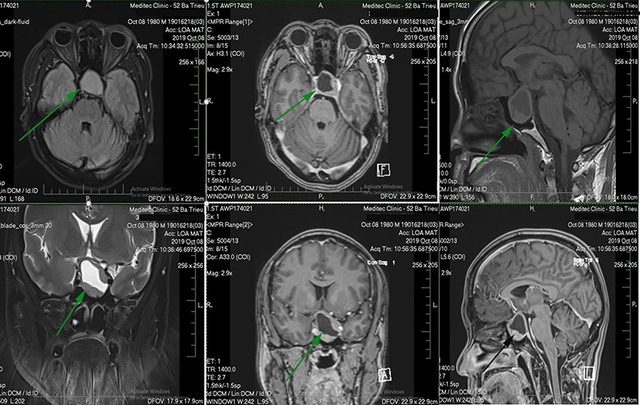

Suy tuyến yên do bị tổn thương thể gây rối loạn nội tiết, căn nguyên của đái tháo nhạt

Kết quả thăm khám và xét nghiệm cho thấy bệnh nhân mắc suy tuyến yên sau phẫu thuật u sọ hầu, là tình trạng rối loạn nội tiết hiếm gặp. Đặc biệt, kết quả xét nghiệm natri máu tăng, cho thấy áp lực thẩm thấu máu tăng và áp lực thẩm thấu niệu giảm. Bệnh nhân được các bác sĩ chẩn đoán mắc suy tuyến yên sau phẫu thuật u sọ hầu, được bác sĩ chỉ định điều trị và hướng dẫn đồng thời thay đổi thói quen sinh hoạt, chế độ dinh dưỡng.

Theo bác sĩ điều trị, trường hợp của anh N. bị đái tháo nhạt. Bệnh không xuất hiện độc lập mà là một phần trong biến chứng suy tuyến yên sau phẫu thuật u sọ hầu. Khi tuyến yên bị tổn thương, hormone chống bài niệu (ADH) suy giảm, khiến cơ thể không giữ được nước, từ đó gây ra tình trạng khát liên tục, đi tiểu nhiều và nước tiểu loãng.